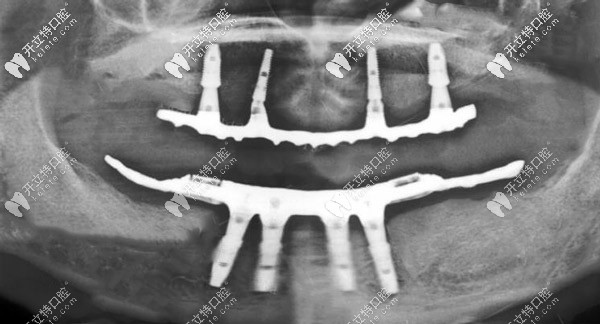

CBCT線片圖▼

ALL-ON-4種植X線片